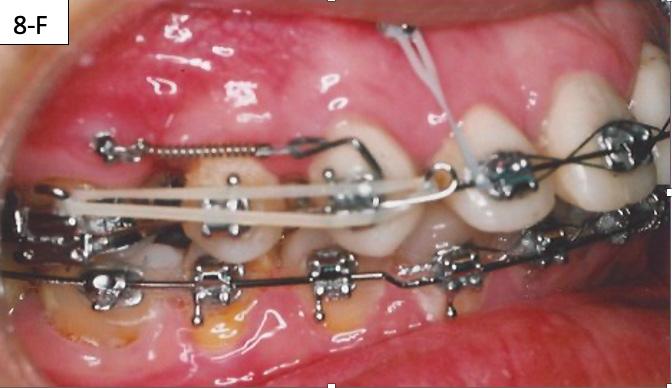

The brackets were bonded on the maxillary incisors and there was a progression of the arch wires a .014 NiTi, a .016 SS and a .018 SS. The progression of the arch wires in the mandible was a .016 NiTi, a .016 SS, a .018 SS and a .018 x 025 SS with the step-down distally to the cuspids. A 1.6 x 8.0 mm Ancor Pro TADs were inserted on the buccal aspect distally to the maxillary lateral incisors to aid the intrusion of the maxillary anterior sextant.8 Maxillary incisors were laced back, to prevent splaying during the intrusion and two links of an elastomeric chain were attached from the TADs to the arch wire. Power arms were bent from a .016 x 022 SS wire and ligature tied to the bracket #13(6) an #24(12).

Closing coil springs were attached from TADs to the power arms. To prevent an undesirable labial moment (flaring) of the maxillary incisors, Class I (labial intra) elastics (¼” – 4.5 oz) were

placed from the buccal hook of the maxillary first molar to the helical loop on the arch wire. The helical loop was fabricated just distally to the maxillary lateral incisors on a. 018 SS arch wire (Figure 8-D, E, F, G).